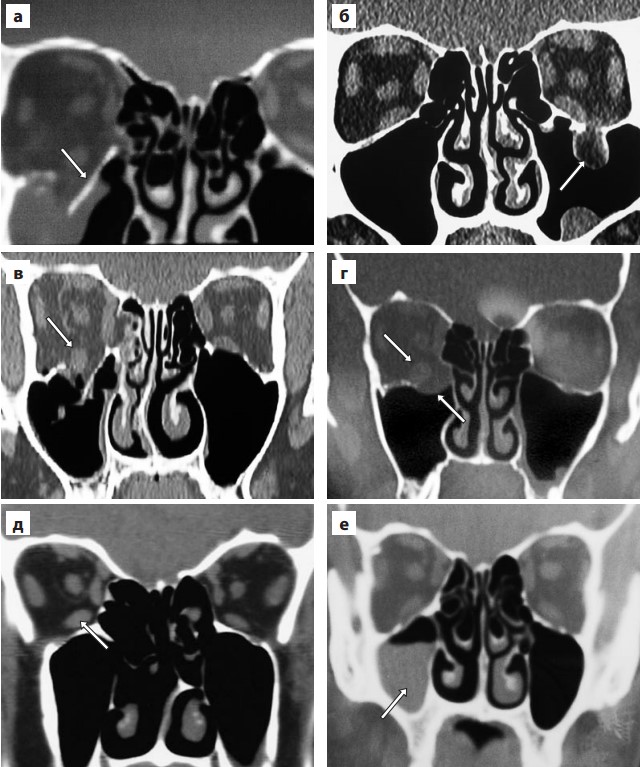

- Обширный костный дефект со смещением отломка (обозначен стрелкой) в пазуху (а)

- Пролапс в верхнечелюстную пазуху ущемленной в «переломе-капкане» орбитальной жировой клетчатки (стрелка) (б)

- Округление в норме уплощенного брюшка нижней прямой мышцы (обозначено стрелкой). Симптом не обладает особой диагностической ценностью при очевидном переломе (в), но весьма информативен при небольших по протяженности повреждениях нижней стенки (г, д)

- Массивное кровоизлияние в верхнечелюстную пазуху, облегчающее диагностику перелома с минимальным смещением отломков.

Косвенные признаки перелома:

- Предлежание мышцы к, казалось бы, неповрежденному дну глазницы. Сочетание этого симптома с характерной клинической картиной свидетельствует об ущемлении футляра глазодвигательной мышцы и окружающих соединительнотканных перемычек в зоне линейного перелома по типу «капкана»

- Симптом «пропавшей нижней прямой мышцы», когда при переломе по типу «капкана» мышца оказывается ущемленной в зоне костного дефекта таким образом, что на корональных КТ-граммах не визуализируется ни в орбите, ни в верхнечелюстной пазухе

- Хорошо различимое на корональной КТ-грамме округление в норме уплощенного брюшка нижней прямой мышцы , свидетельствующее об утрате ее костной и соединительнотканной поддержки. В эксперименте на кадаверных орбитах установлено, что при площади перелома до 1 см округление брюшка нижней прямой мышцы возникает лишь при разрыве надкостницы (что чревато поздним энофтальмом и требует раннего оперативного вмешательства). При площади перелома 4 см брюшко округляется и без травмы надкостницы, но при ее разрыве симптом более выражен.

- Наличие свободной жидкости в параназальном синусе